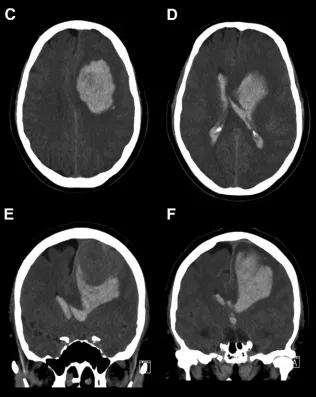

患者入院约6小时后病情急剧恶化,在转诊至上级神经外科中心途中突发意识丧失。紧急抢救后生命体征趋于稳定,抵达后立即进行CT复查,结果显示原病灶周围出现大量脑实质内出血及脑室内出血,确诊为良性脑膜瘤相关的"两阶段"复发性出血事件。

急诊手术与病理结果

医疗团队实施紧急开颅手术,完整切除实体肿瘤及周围血肿,同时放置脑室外引流管缓解颅内高压。术后患者恢复良好,引流管按计划拔除,未出现脑积水并发症。三个月随访显示右侧偏瘫症状显著改善,MRI确认肿瘤完全切除,颅内无出血迹象。

术后病理检查诊断为过渡型脑膜瘤(WHO I级),肿瘤未侵犯脑实质,但可见急性出血区和含铁血黄素沉积,提示既往存在微出血史。病理学检查未发现病理性血管、梗死、坏死等非典型特征。